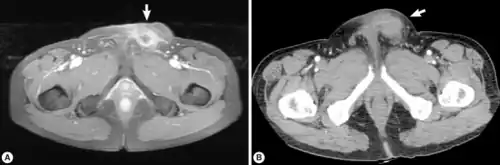

Infection of S. erinaceieuropaei is termed sparganosis.[8] However, this term encompasses the entire genus Spirometra and is not specific to S. erinaceieuropaei. Sparagnosis due to S. erinaceieuropaei is rare.[9] Adults Spirometra typically infect dogs, cats and other carnivores.[16] They will reproduce in their intestines, and the eggs will be shed in their feces.[17] Although humans can get infected with this parasite, they cannot contract it from the feces of an infected cat or dog.[18] Sparagnosis refers specifically to the infection with Spirometra larvae and is endemic in animals but a rare condition for humans.[8] In humans, the larvae are typically found in subcutaneous tissues or muscle, and will form slowly growing masses.[16] Sometimes infection in humans can also involve genitourinary tract, pleural or abdominal cavity, and scrotum. Infection can also involve the central nervous system, but this is even less common. When the central nervous system is involved, symptoms may occur as many as twenty years after infection.[19] These can include weakness, headache, seizures, numbness, tingling, or abnormal skin sensations.[16] Because the masses are typically slow growing, they often resemble tumors on radio graphs.[19] Additionally, larvae may create migratory lesions (also called wandering lesions) within tissue. These lesions are a large sign of infection.[19]

Infection in humans can be detected via imaging, but because larvae may appear as a mass, most diagnosis occurs after surgical removal.[16][8][9] Diagnosis in animals is typically done by characterizing eggs in fecal matter. Since most tapeworm infections within the genus Spirometra have similar egg morphology, species characterization is not typical. Animals are usually treated with anti-worm medications, such as Praziquantel.[10] Surgical removal is the most common treatment in humans, as well as treatment by anti-worm medication such as Albendazole.[11]